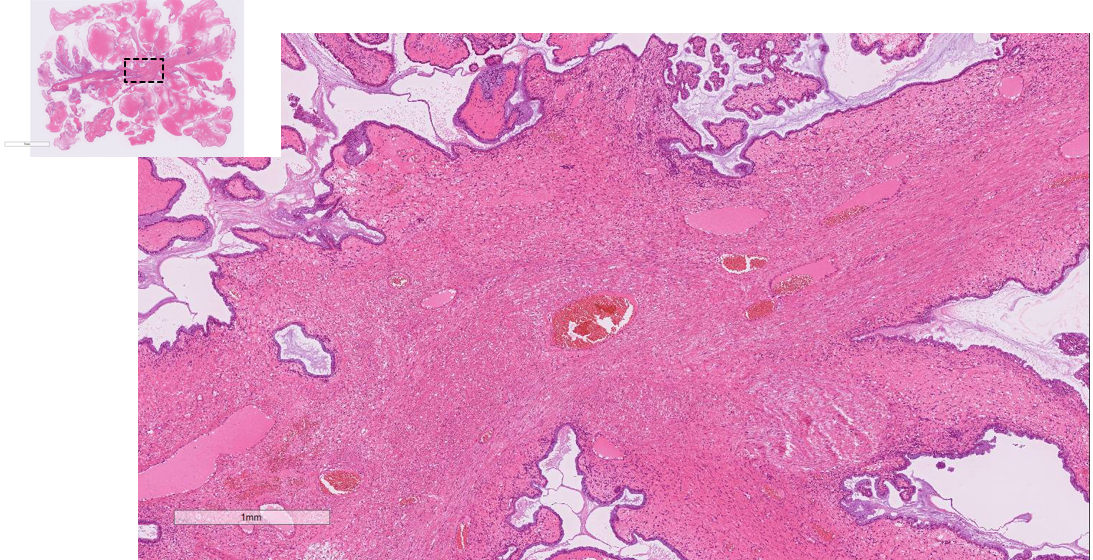

• HE(x20) Stalk 部分拡張血管や dense な線維性結合組織成分を認める

• HE(x40) 辺縁部分 ①浮腫状間質を取り囲み、腫瘍細胞が低乳頭状に増殖する。 矢印:腹腔内に粘液が漏出

• HE(x100) 辺縁部分 ② 細胞質内粘液を有する内頸部型の粘液円柱上皮が低乳頭状に増殖。

矢印:上皮下には内膜間質様の細胞密度の高い間質を認め、間質浸潤はない。

• HE(x20) 虫垂虫垂には腫瘍性病変を認めない